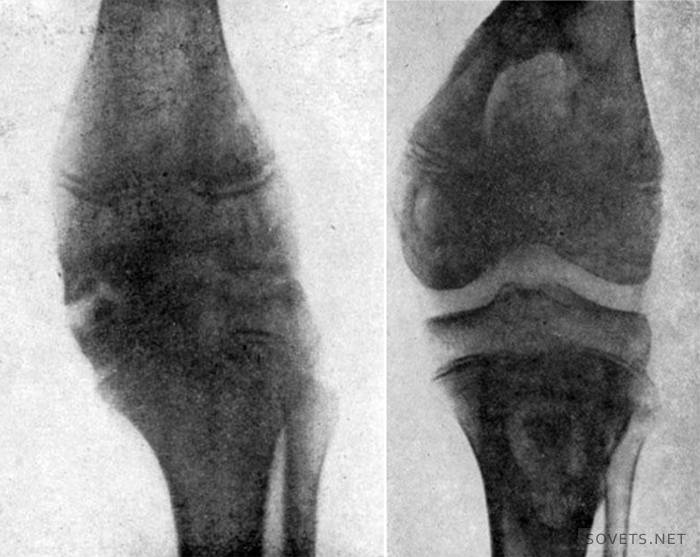

- Una variedad de defectos óseos.Por ejemplo, las formas en forma de X de las piernas inferiores provocan una gran carga en las partes externas de la articulación, y las en forma de O en las internas (ver foto). En tales casos, el dolor y la deformación del tejido del cartílago y la articulación en su conjunto son inevitables.

Con la artrosis de primer grado, no se produce deformación del hueso de la rodilla, solo es posible un estrechamiento del espacio articular, notable en la imagen. La foto 3 muestra una articulación de la rodilla sana, la foto 4 muestra un espacio articular estrecho.

Con la artrosis de segundo grado, el dolor en la rodilla se vuelve tan fuerte que restringe el movimiento. Viajar largas distancias se vuelve casi imposible. Es necesario dar un descanso prolongado a la articulación enferma para poder seguir adelante. Se produce deformación, se escucha un fuerte crujido en la rodilla durante el movimiento, se observa cojera.

El espacio articular se estrecha aún más, el hueso crece y aparecen osteofitos (espigas). Se puede acumular líquido en la rodilla si se une la sinovitis: inflamación del revestimiento interno de la articulación.

Este es el grado más difícil de gonartrosis (artrosis), se observa dolor tanto al caminar como en reposo completo. La pierna está casi inmóvil. La deformidad de los huesos de la rodilla es pronunciada, el espacio articular puede estar completamente ausente.